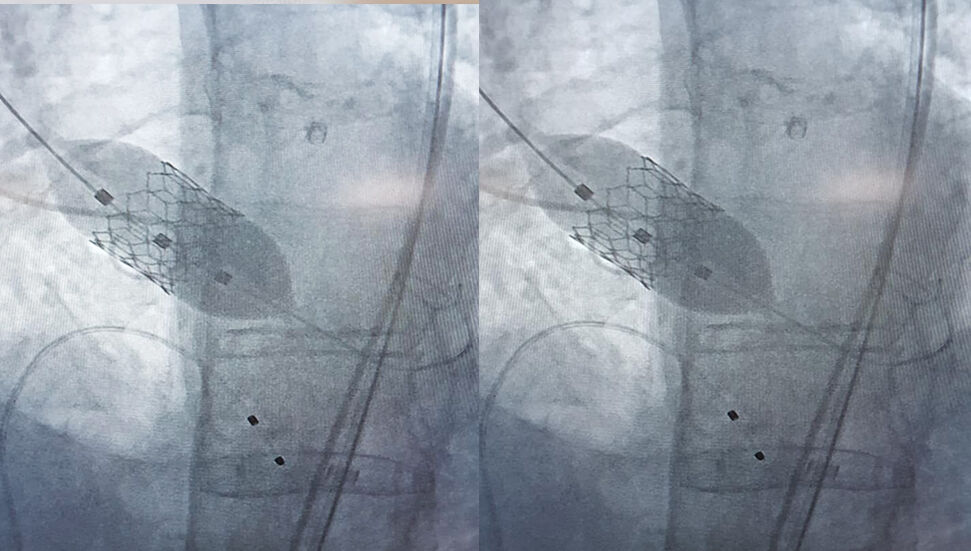

“Lefkoşa Devlet Hastanesi'nde 83 ve 88 yaşında iki hastamıza daha başarılı bir şekilde TAVI işlemini (kasıktan girilerek ameliyatsız yöntemle aort kapak değişimi) ekipçe başarılı bir şekilde gerçekleştirmenin haklı gururunu, huzurunu ve mutluluğunu yaşıyoruz.”